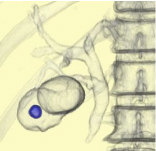

CTで撮影した心臓の血管の立体像です。 -

左と同じ患者様です。(真ん中に狭い血管が見つかりました) -

同じ患者様のカテーテル検査の写真です。(CTと同じ所に狭い部分があります) -

狭くなっている部分にステントと呼ばれる金属の筒を入れて血管の流れが良くなりました。